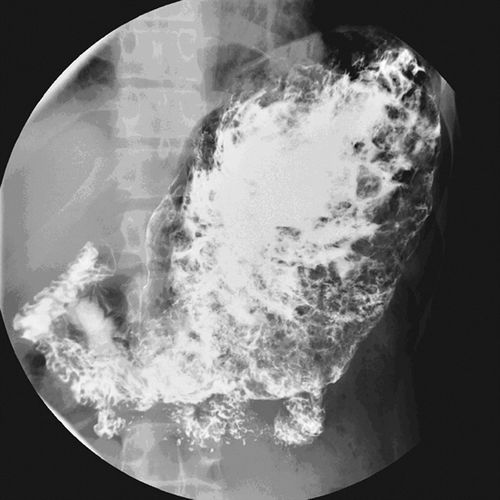

2007年,宾夕法尼亚大学医学院的学者在《美国放射学杂志》上发表了一项研究,去观察那些大胃王比赛冠军以及相关职业选手的胃,在进食后会有怎样的变化。

结果发现这些人群在吃了很多的热狗的情况之下,没有出现急性胃穿孔等大家想象中最危险的场景。在实验过程中,这些大胃王吃了很多的热狗后,胃内并不会快速蠕动,而是逐渐形成一个非常松弛的囊,随后容纳越来越多的食物。

图 | 参考文献